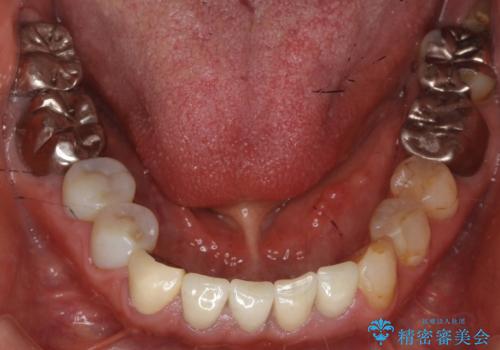

精査したところ、被せ物を入れたばかりの右下の小臼歯(右下5)は不可逆性歯髄炎により神経をとる処置(抜髄)が必要な状態でした。

根管治療後、セラミッククラウンによる補綴治療を行いました。

根管治療により痛みがなくなり、ご安心頂けました。

セラミッククラウンの自然な仕上がりにも喜んで下さいました。

クラウンの種類:オールセラミッククラウン エコノミー